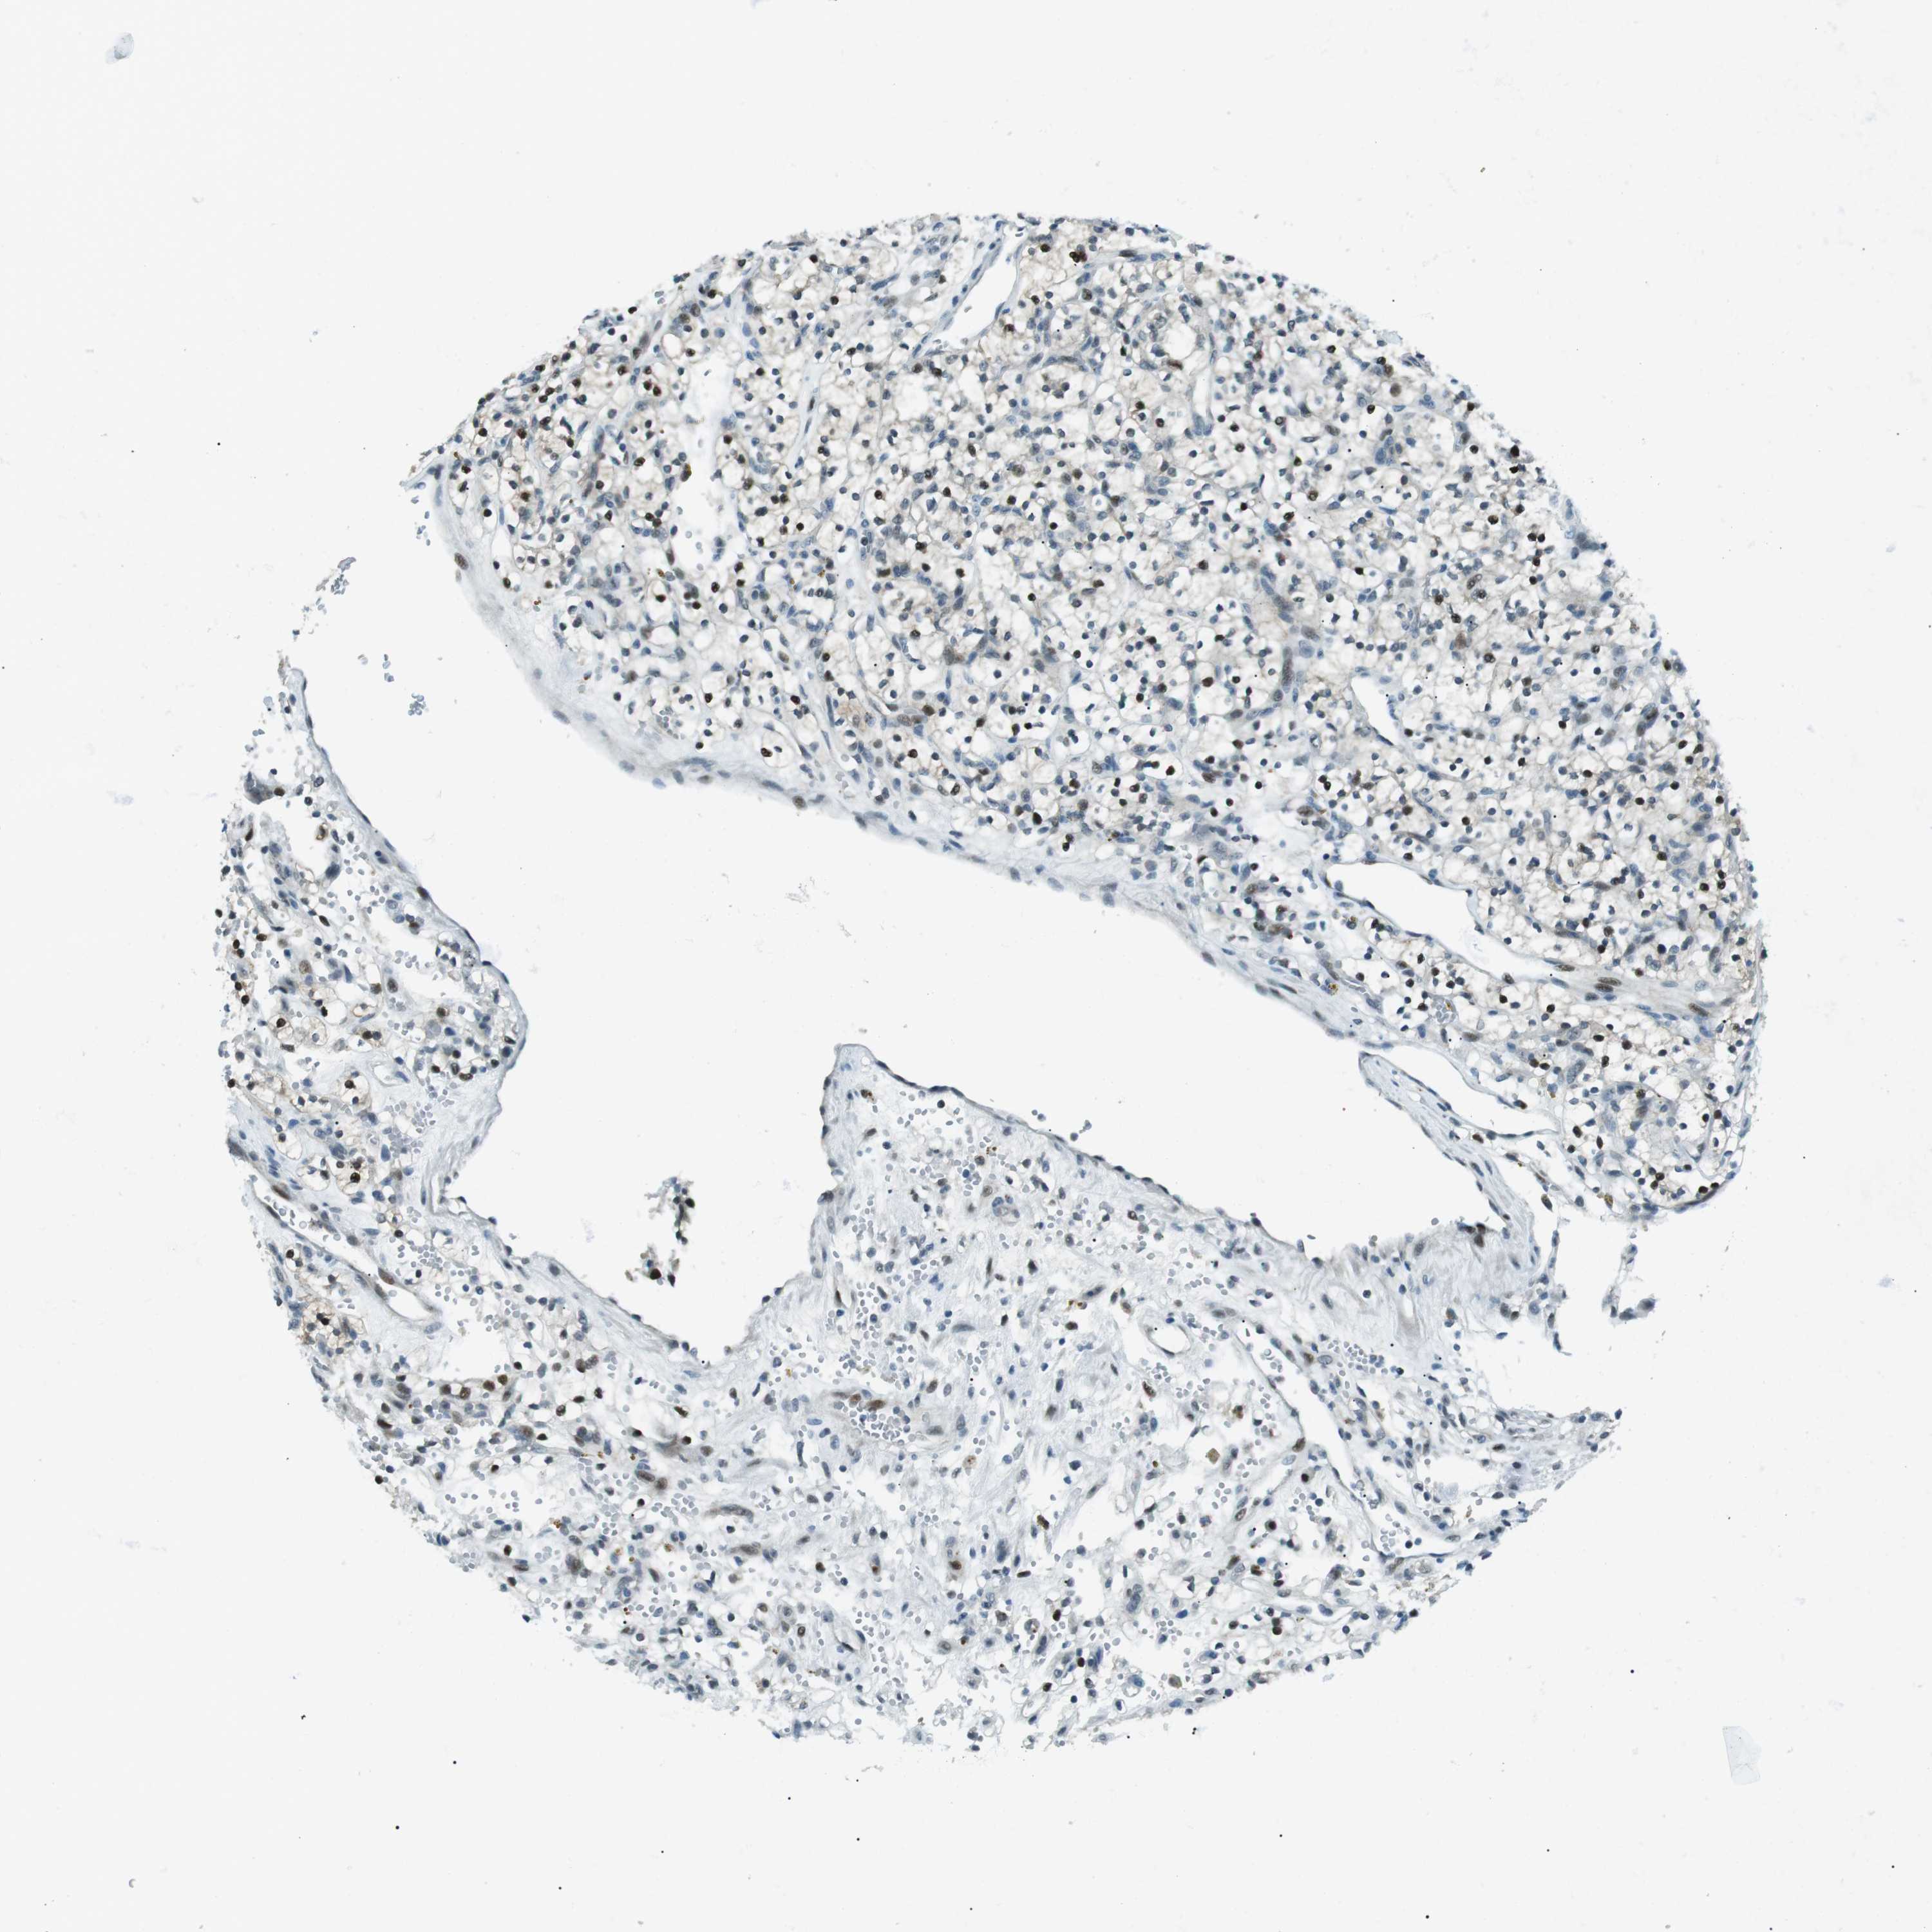

Renal cancer

Kidney chromophobe

KIDNEY CHROMOPHOBE (TCGA) - Interactive survival scatter ploti

The Survival Scatter plot shows the clinical status (i.e. dead or alive) for all individuals in the patient cohort, based on the same data that underlies the corresponding Kaplan-Meier plots. Patients that are alive at last time for follow-up are shown in blue and patients who have died during the study are shown in red.

The x-axis shows the expression levels (FPKM) of the investigated gene in the tumor tissue at the time of diagnosis. The y-axis shows the follow-up time after diagnosis (years). Both axes are complimented with kernel density curves demonstrating the data density over the axes. The top density plot shows the expression levels (FPKM) distribution among dead (red) and alive patients (blue). The right density plot shows the data density of the survived years of dead patients with high and low expression levels respectively, stratified using the cutoff indicated by the vertical dashed line through the Survival Scatter plot. This cutoff is automatically defined based on the FPKM cutoff that minimizes the p-score. The cutoff can be changed by dragging the vertical line or by entering a cutoff value in the square labeled "Current cut-off".

Under the Survival Scatter plot the p-score landscape (black curve; left axis) is shown together with dead median separation (red curve; right axis). Dead median separation is the difference in median mRNA expression between patients who have died with high and low expression, respectively. It is calculated as follows: median FPKM expression of dead patients with high expression - median FPKM expression of dead patients with low expression. This is intended to aid the user in visually exploring custom cutoffs and the associated p-scores and dead median separation.

Individual patient data is displayed and can be filtered by clicking on one or more of the category buttons on the top of the page. Categories describing expression level and patient information include: high, low, alive, dead, female, male and tumor stages. The scale of the x-axis can be toggled between linear and log-scale by clicking on the "x log" button. Mouse-over function shows TCGA ID, patient information and mRNA expression (FPKM) for each patient.

& Survival analysisi

Kaplan-Meier plots summarize results from analysis of correlation between mRNA expression level and patient survival. Patients were divided based on level of expression into one of the two groups "low" (under cut off) or "high" (over cut off). X-axis shows time for survival (years) and y-axis shows the probability of survival, where 1.0 corresponds to 100 percent.

PJA1 is not prognostic in Kidney Chromophobe (TCGA)